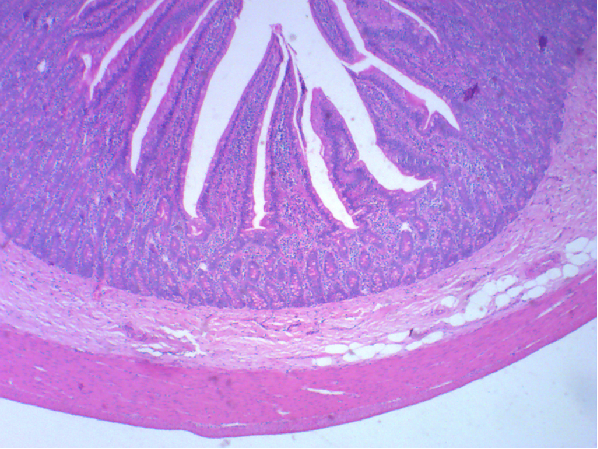

图4. 十二指肠光镜像(HE染色)

十二指肠壁从内向外依次为黏膜、黏膜下层、肌层和外膜。其特点是在黏膜下层有大量十二指肠腺,为黏膜性腺,开口于小肠腺底部,分泌黏稠的碱性黏液(pH8.2-9.3),保护十二指肠免受胃酸的侵蚀,也是小肠内碱性环境形成的原因之一。